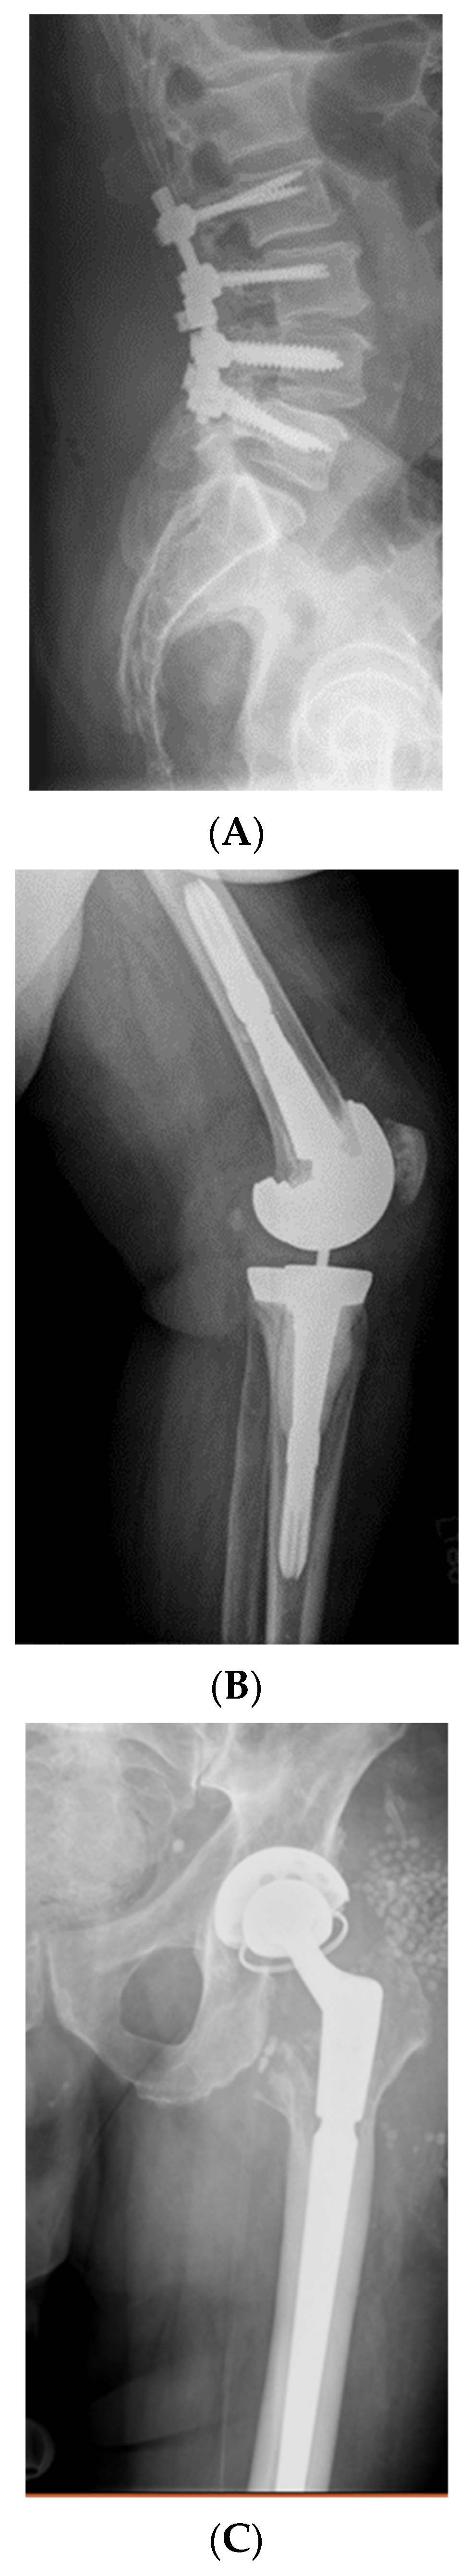

3.1. Case Studies of Intravenous Bacteriophage Therapy in Biofilm Infections

3.2. Case Studies of Direct Injection of Bacteriophages to Biofilms with Surgical Intervention

- Doub, J.B.; Ng, V.Y.; Johnson, A.J.; Slomka, M.; Fackler, J.; Horne, B.; Brownstein, M.J.; Henry, M.; Malagon, F.; Biswas, B. Salvage Bacteriophage Therapy for a Chronic MRSA Prosthetic Joint Infection. Antibiotics 2020, 9, 241. [Google Scholar] [CrossRef]

- Cano, E.J.; Caflisch, K.M.; Bollyky, P.L.; Van Belleghem, J.D.; Patel, R.; Fackler, J.; Brownstein, M.J.; Horne, B.; Biswas, B.; Henry, M.; et al. Phage Therapy for Limb-threatening Prosthetic Knee Klebsiella pneumoniae Infection: Case Report and In Vitro Characterization of Anti-biofilm Activity. Clin. Infect. Dis. 2020, ciaa705. [Google Scholar] [CrossRef] [PubMed]